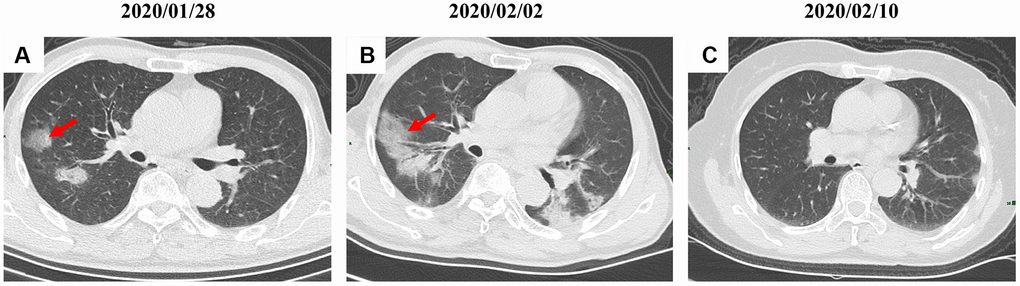

By Mar 23, 2020, 60 (60/66, 91%) patients had been discharged. 6 (6/66, 9%) patients were still in hospital, and two patients had died because of ARDS. Patient 1, 78-year-old man with hypertension, who died on day 15 after admission (Figure 1B). Patient 2, 47-year-old man with type 2 diabetes, whose CT scan presented rapid radiology progression (Figure 3A, 3B). The radiological change of COVID-19 pneumonia develops fast during the first seven days (Figure 3C, 3D). Some of patch lesion could be absorbed and change into reticular spline lesion (Figure 4A, 4B). Meanwhile, some patients achieved rapid recovery with significant improvement of CT sign (Figure 4C, 4D) and clinical symptoms. We also did some CT follow-up scans for few patients, which showed the aggravated progression of disease since admission and rapid recovery after treatment (Figures 5 and 6). Disappearance of lesions and significant improvement of clinical symptoms were observed in two patients (Figure 5: a 54-year-old male patient; Figure 6: a 54-year-old female patient).

Figure 5. A serial CT images after admission of a 54-year-old male patient. (A) Patch ground-glass opacity was observed in the middle right lobe. (B) 5 days later, significant larger patch ground-glass opacities were observed in bilateral lungs. (C) Follow-up CT scans on day 13 after admission show a remarkable improvement. Typical lesions were marked with red arrows.